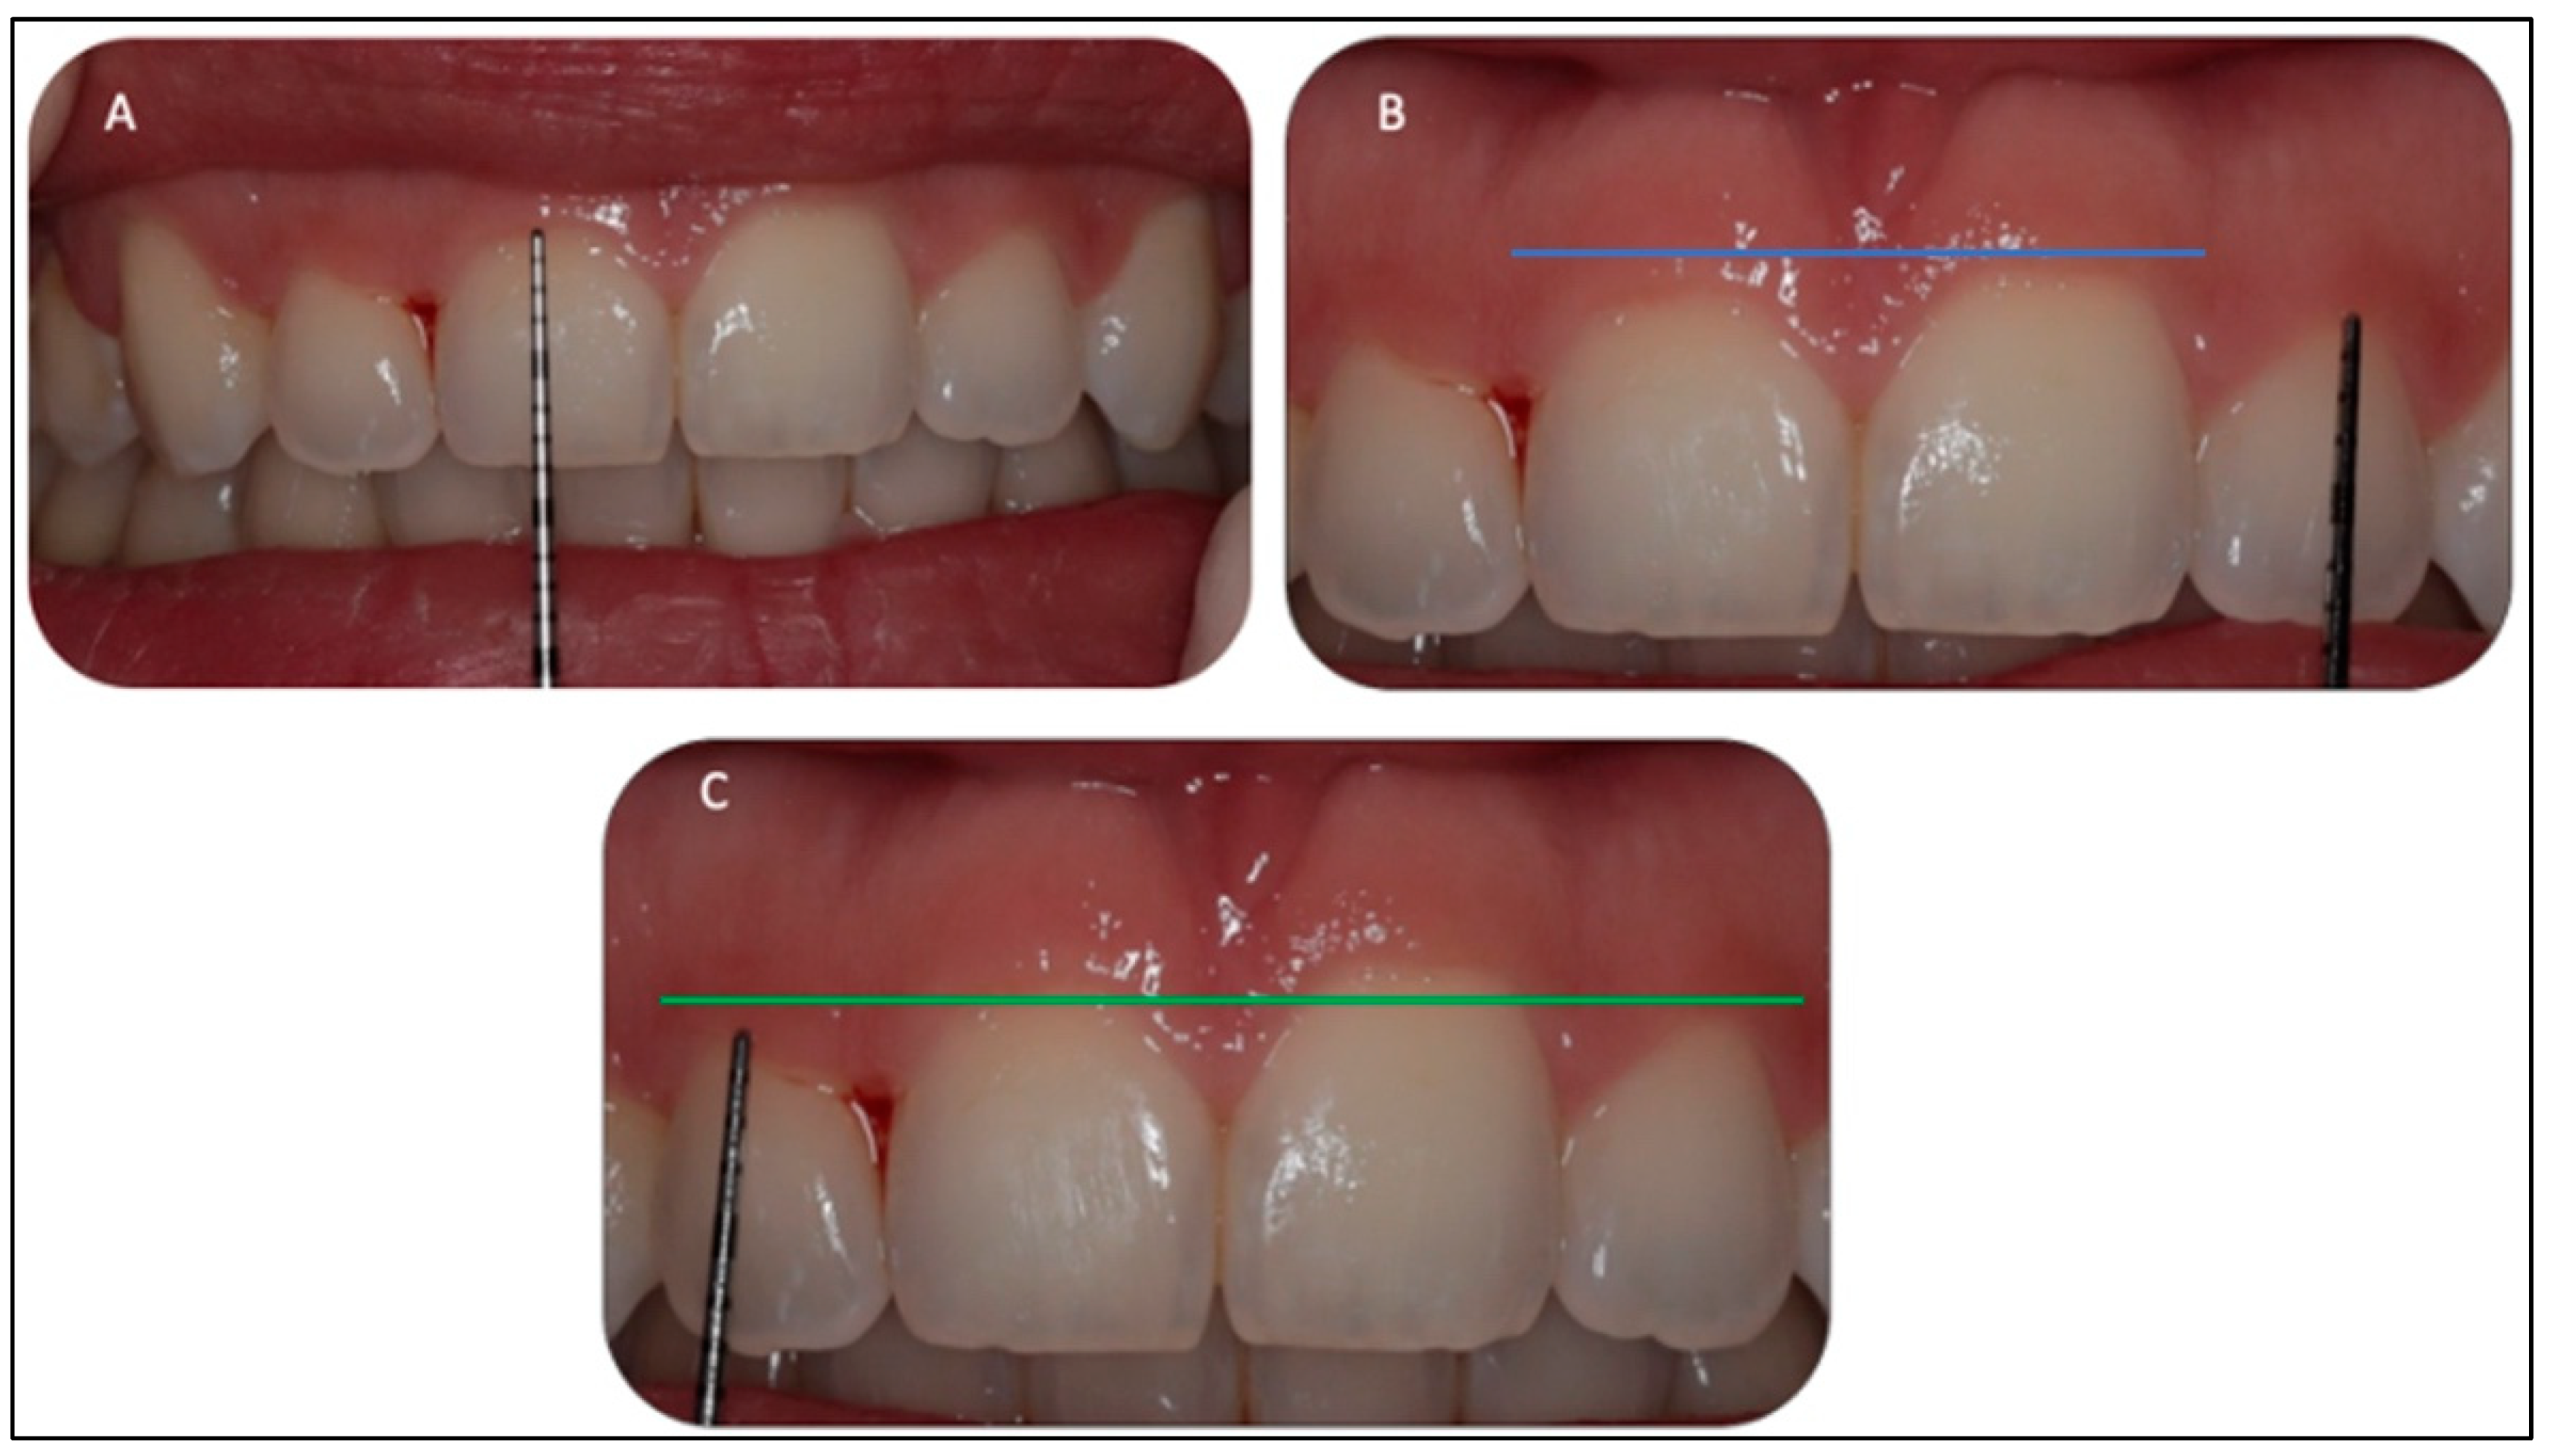

2.5.1. Gingivoplasty Procedure

2.5.2. Upper Midline Frenectomy Procedure